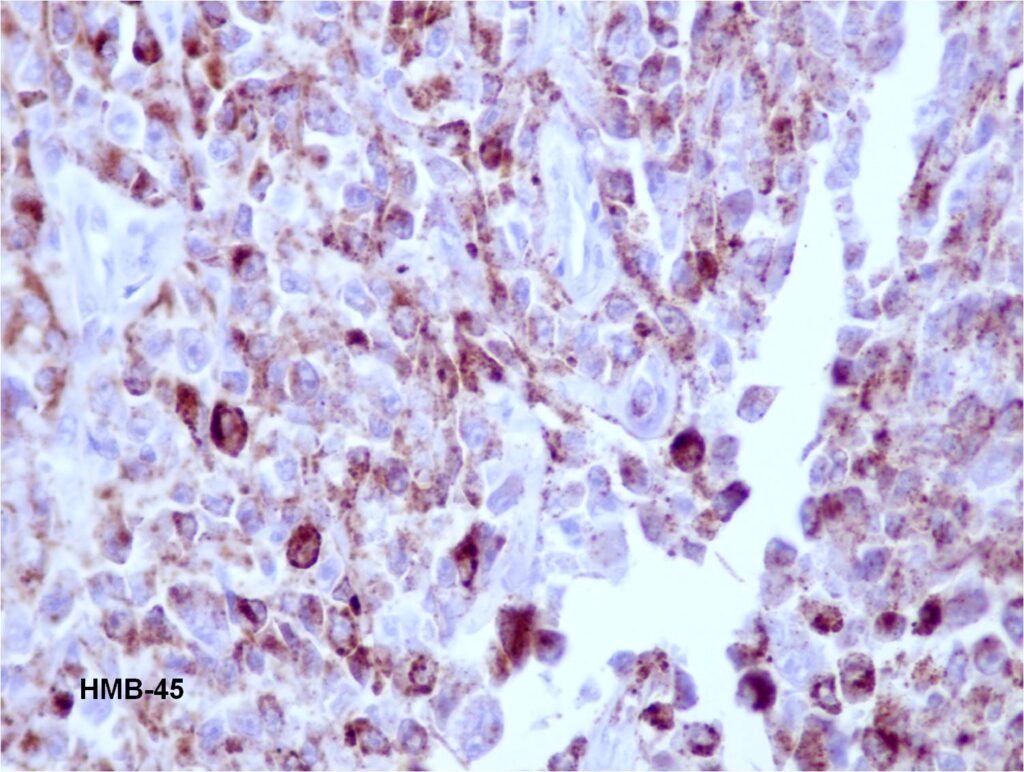

Fig. 8

Fig. 9

Fig. 8 & 9: Immunomarkers for melanoma antigens S100 (Fig. 8) and HMB45 (Fig. 9) were positive.